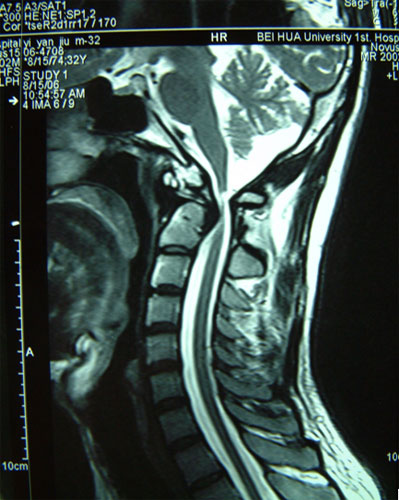

寰枢关节不稳脱位         高位颈脊髓受压迫,瘫痪呼吸困难